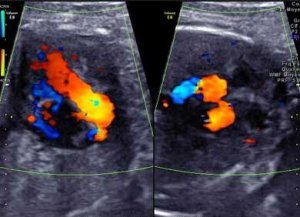

Патологію серцевого клапана можна визначити при проведенні Ехокг та процедури електрокардіографії. В якості додаткового варіанту використовується рентген грудної порожнини. Але, незалежно від ефективності застосовуваних методик, найбільш інформативним можна вважати саме ультразвукове обстеження серцево-судинної системи. При такому варіанті гарантовано отримання найбільш точних даних. За допомогою ультразвуку стає доступною можливість оцінки стану всіх порожнин серця, а також тристулкового клапана.

Найкращий метод діагностики

Технічні засоби, що застосовуються в сучасній медицині, що дозволяють без особливих труднощів діагностувати трикуспидальную регургітацію.